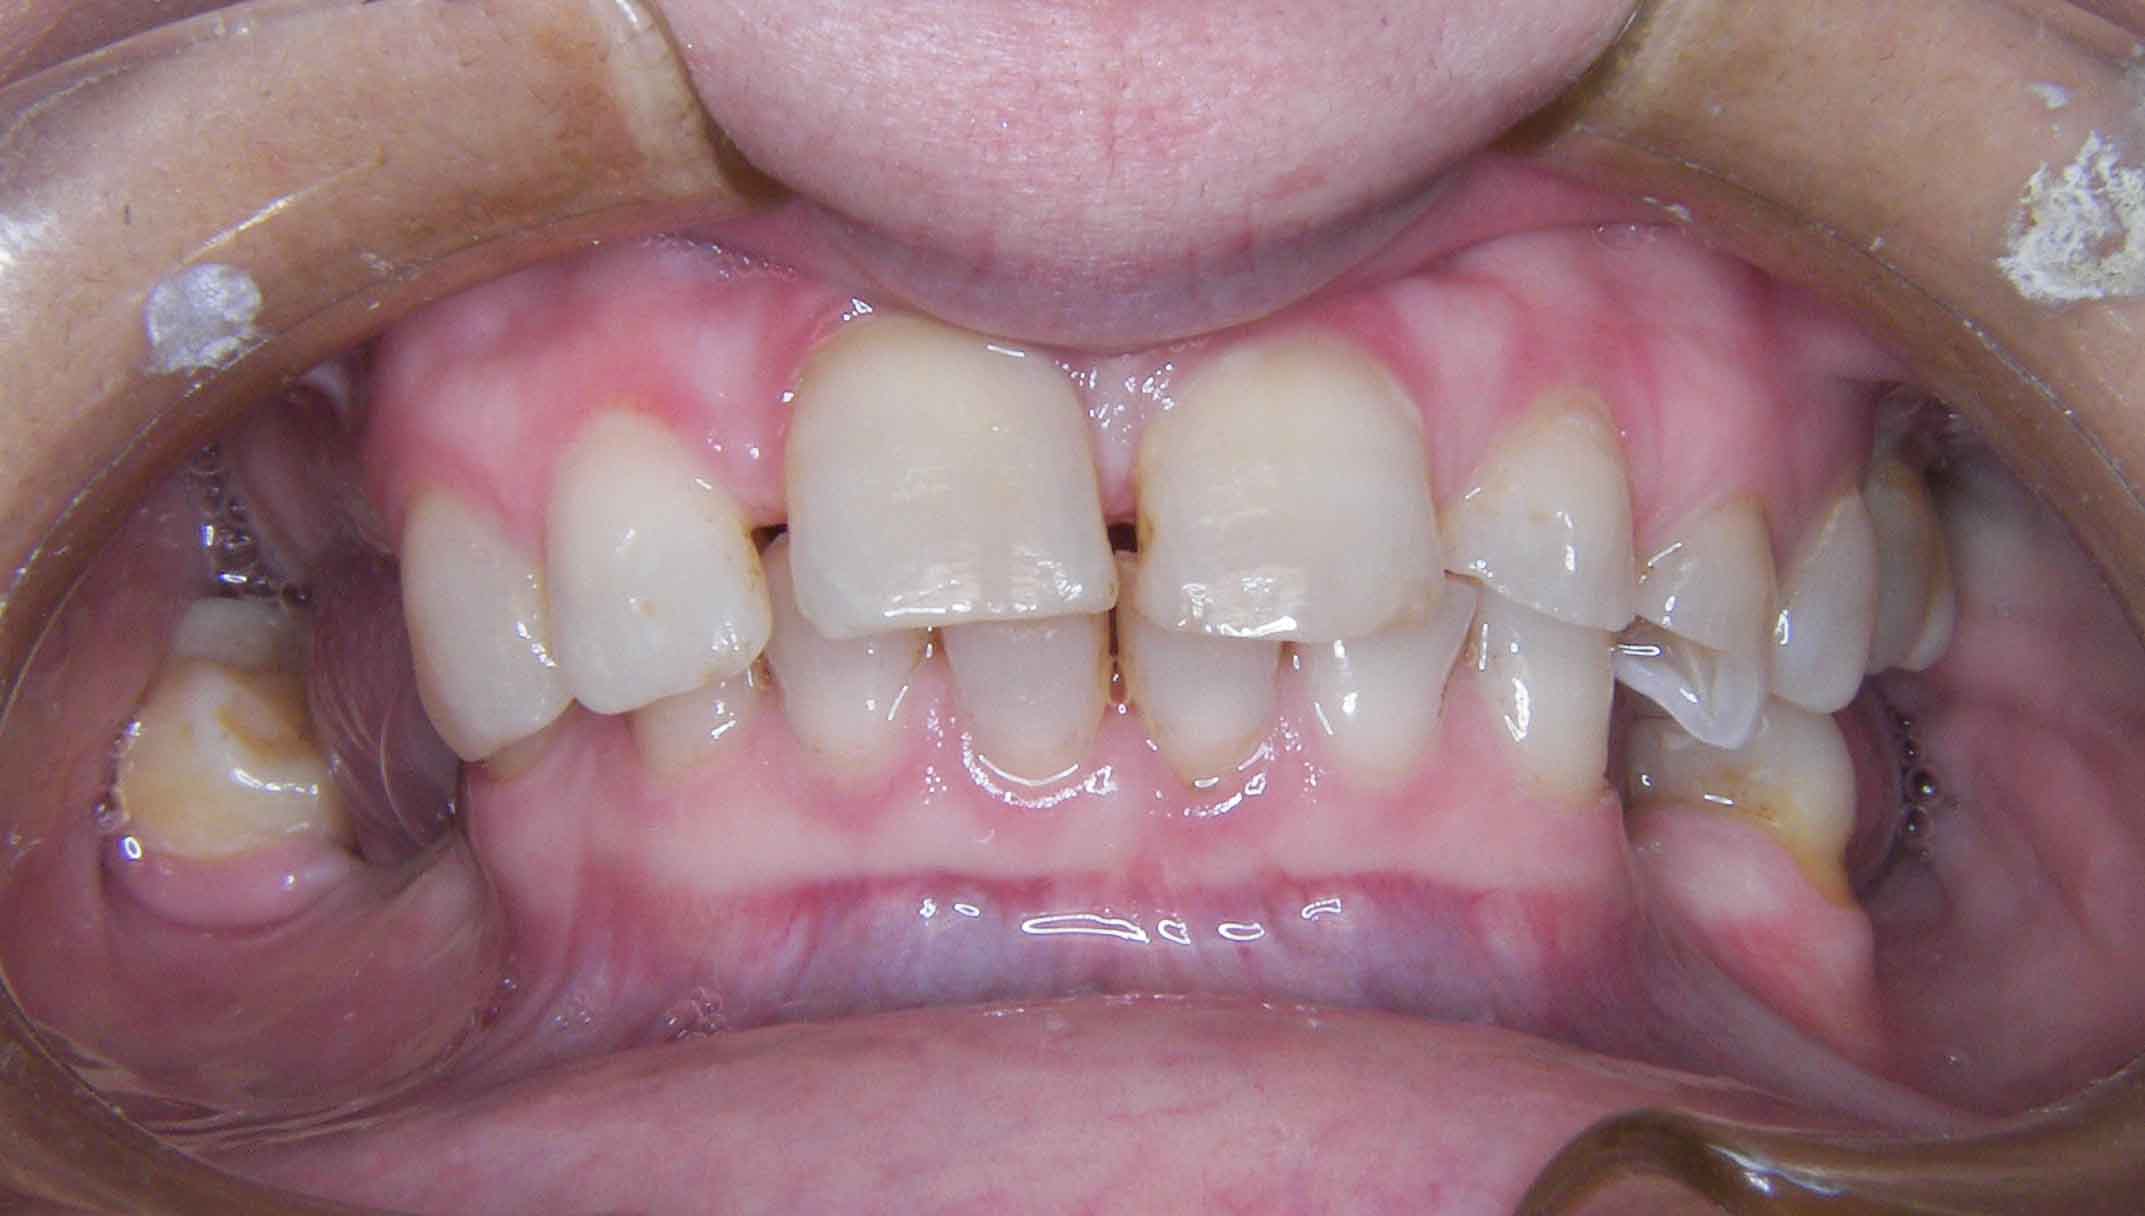

Paciente com limitações funcionais e estéticas graves

Reabilitação Complexa - Tratamento

Mantiveram-se os dentes naturais remanescentes que tinham bom prognóstico e com Aparelho Ortodôntico fixo foram corrigidas as suas posições.

Posteriormente foi feita cirurgia para colocação de alguns Implantes.

Finalizou-se com colocação de Coroas Cerâmicas.